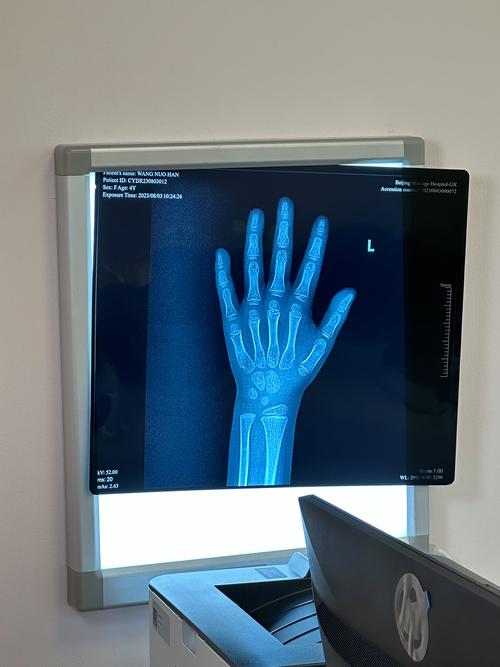

儿科学是一门研究胎儿至青少年时期生长发育、疾病防治的综合性医学学科,强调对儿童生理、病理特点的深入理解,临床实践以儿科常见病、多发病及危重症诊治为核心,其研究方向涵盖新生儿学、儿童心血管病学、儿童血液肿瘤学、儿童神经病学等多个亚专业,近年来在儿童遗传代谢病、发育行为儿科学等领域发展迅速,医学影像学则主要利用X线、CT、MRI、超声及核医学等技术进行疾病诊断,研究方向包括影像诊断、介入放射学、分子影像学等,与临床各学科紧密协作,尤其在肿瘤精准诊疗、神经系统疾病影像分析等方面具有独特优势。

初试科目为英语、专业课(医学影像学综合)及政治,专业课内容包括影像诊断学(X线、CT、MRI、超声等技术的原理与应用)、各系统疾病影像表现(如肺部结节、脑肿瘤、骨骼病变等)、介入放射学基础及辐射防护知识,复试注重影像阅片能力、病例分析及科研设计,常采用影像图片判读、学术答辩等形式。

- 掌握各种影像技术的成像原理及适应症,熟悉正常解剖变异及常见疾病的典型影像特征。

- 大量练习阅片,可通过病例库(如Radiopaedia)积累经验,重点关注儿科、神经、肿瘤等领域的影像诊断要点。